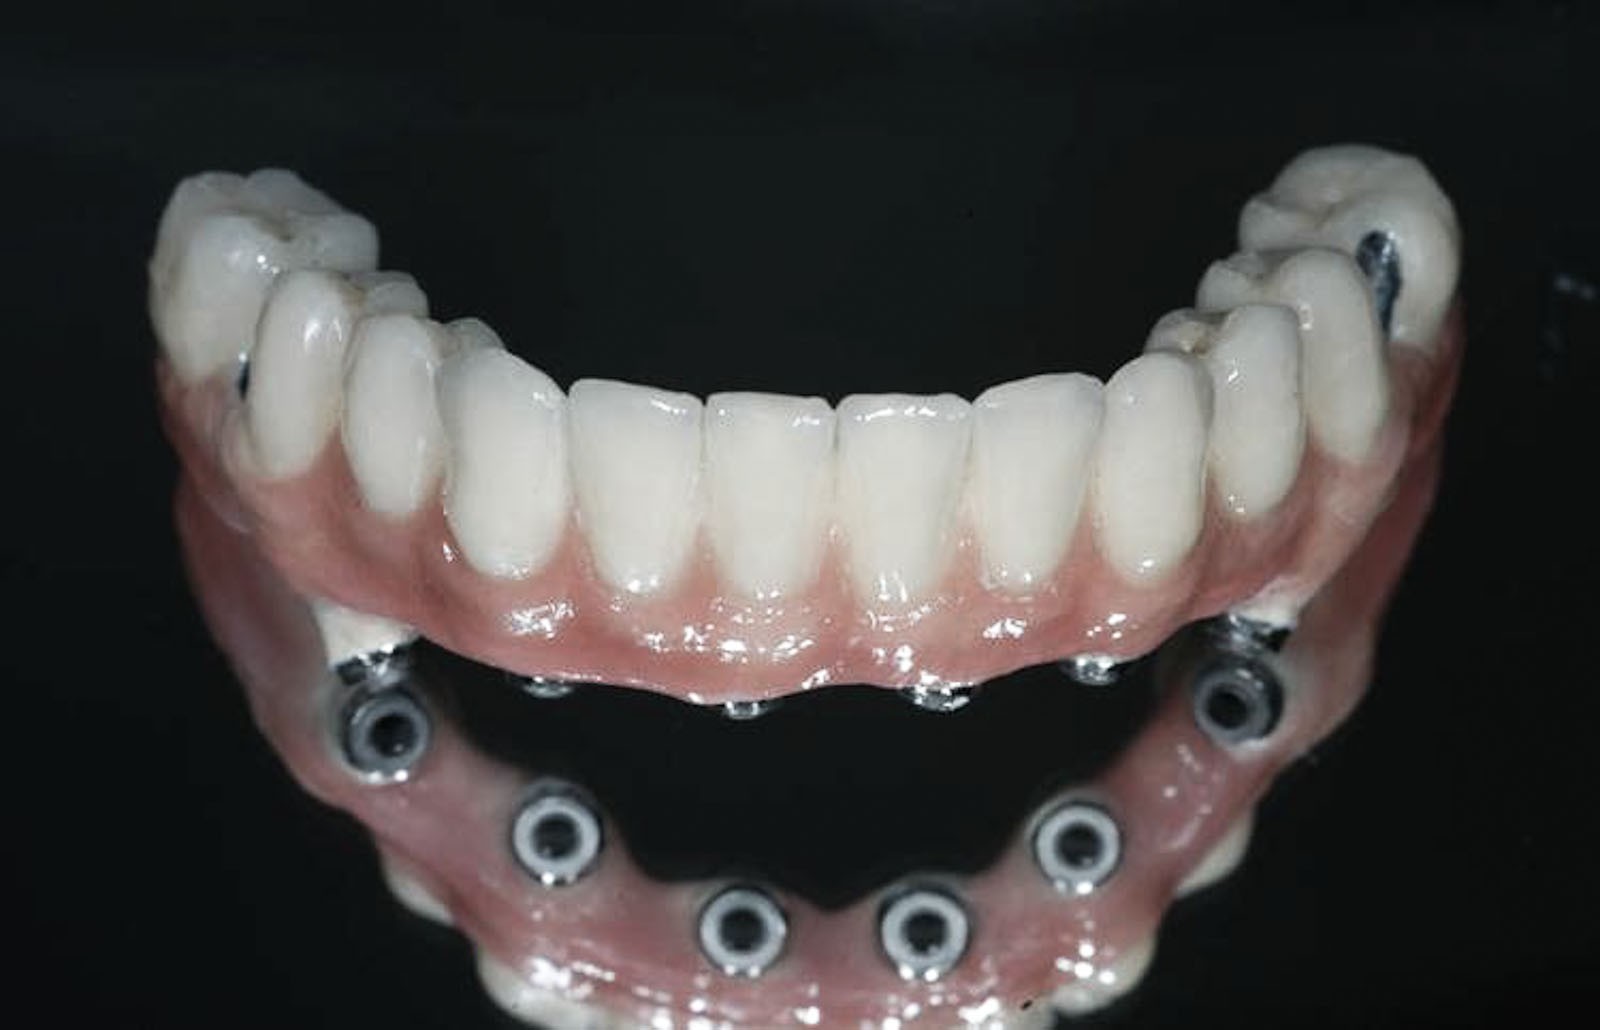

W zależności od stanu podłoża kostnego, jego anatomii oraz wskazań biomechanicznych istnieje kilka systemowych rozwiązań implantologicznych dla bezzębnych pacjentów. Technologicznie mamy kilka sposobów rekonstrukcji protetycznej utraconych zębów na fundamencie wszczepionych implantów

Mosty montowane na stałe na implantach

Technologia konstrukcji mostów protetycznych uzależniona jest z kolei od ilości i rodzaju implantów użytych jako fundamentu dla planowanych uzupełnień protetycznych.

ROZWIĄZANIA PROTETYCZNE ALL-ON-4

Na implantach wszczepionych zgodnie z protokołem all-on-4 możliwe są do wykonania stabilne mosty, jak również ruchome protezy typu nakładowego. Uproszczenie i optymalizacja rozwiązań protetycznych możliwa jest dzięki zastosowaniu kątowych łączników typu MultiUnit (17°, 30°), które po przykręceniu do pochylonych implantów umożliwiają łatwe mocowanie mostu i obsługę serwisową pacjenta.